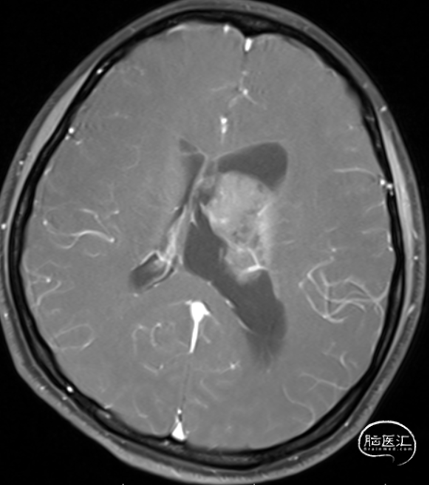

现病史:患者1年前无诱因出现间断头痛,不伴随恶心呕吐等,起初未在意。1个月前上述症状加重,伴随恶心,在当地医院检查CT发现左侧脑室内占位病变,左侧脑室扩大。家人为求彻底治疗来我院,门诊以“1. 左侧脑室内占位;2. 左侧脑室积水”为诊断收入我科。

T1

头部磁共振提示:左侧侧脑占位病变,增强后不染色

中枢神经细胞瘤是WHO Ⅱ级神经上皮脑室内肿瘤,具有独特的影像学特征,表现为侧脑室内大小不等且弱强化的异质肿块,肉眼表现为易碎的灰色肿瘤,典型的附着点包括:Monro孔周围(最常见)50%,侧脑室和第三脑室15%,侧脑室15%,第三脑室5%。该病通常见于年轻患者,手术切除是标准治疗方法。如果可以实现完全切除,通常预后良好。